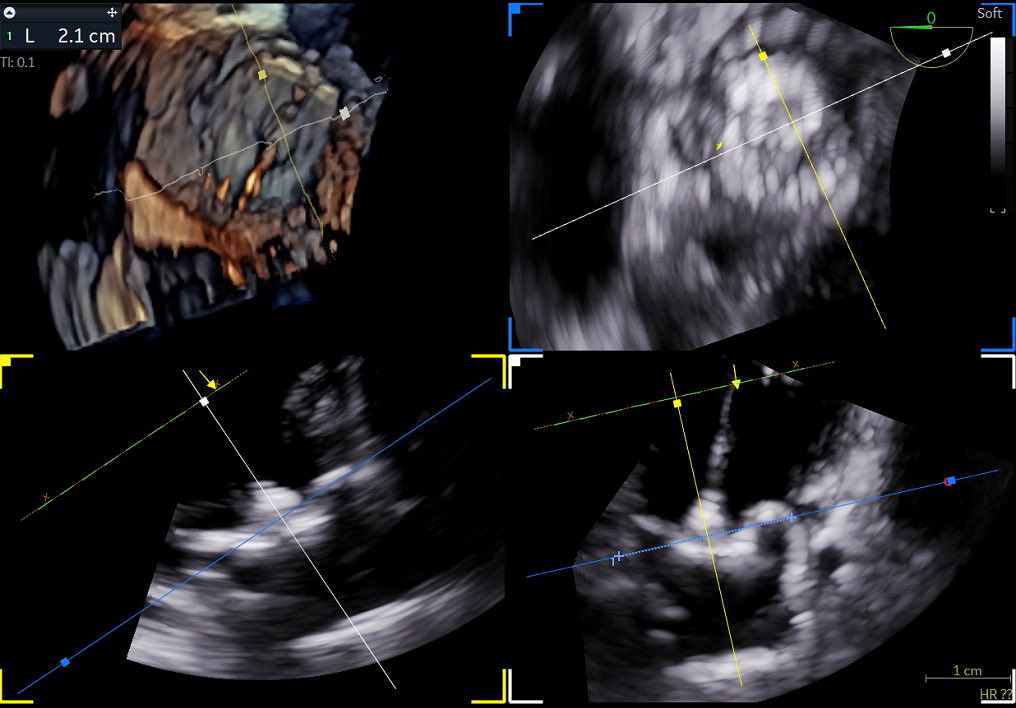

Nuvision Nav catheter @JNJMedTech, first case in New Jersey @RutgersNJMS, @UnivHospNewark in a concomitamment PFA and WATCHMAN procedure, great images and streamline.

English